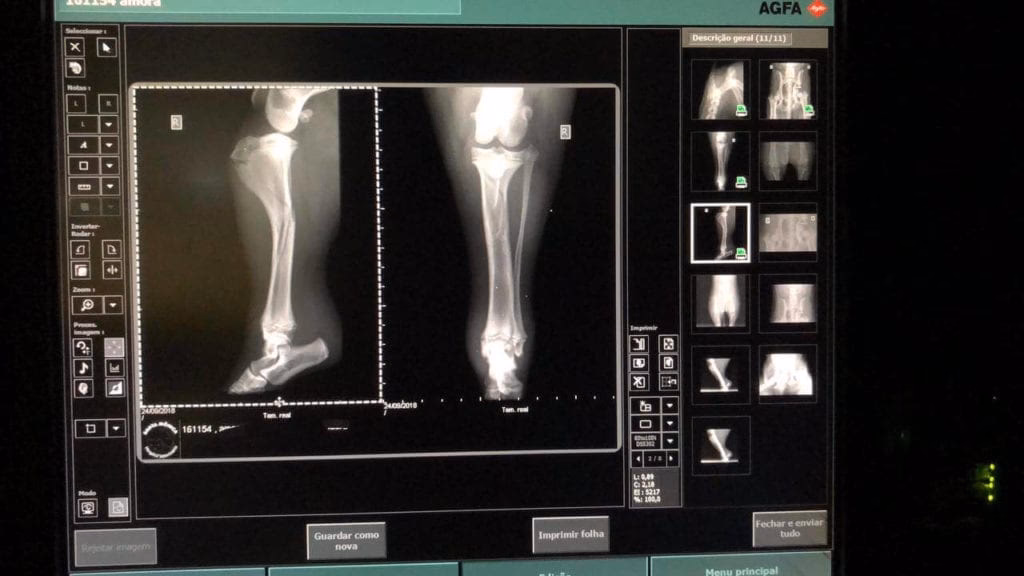

- Radiografías: Son la herramienta fundamental y de primera línea para la evaluación de estructuras óseas. Permiten identificar fracturas, luxaciones, signos de enfermedades degenerativas articulares, tumores óseos y anomalías del desarrollo. Su rapidez y accesibilidad las hacen indispensables.